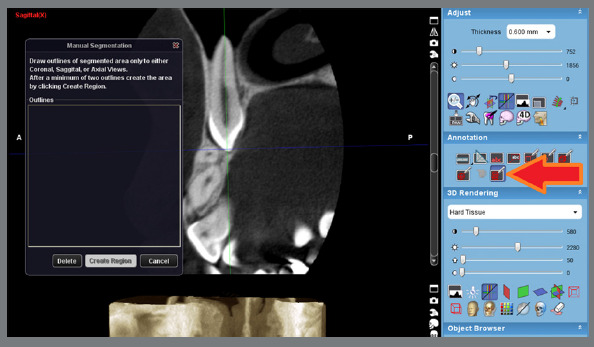

Methods: This cross-sectional study was performed on cone-beam computed tomography (CBCT) scans of 100 patients (49 females and 51 males) with unilateral maxillary canine impaction. The images were loaded in Planmeca Romexis Viewer, and root layers between the cementoenamel junction and apex were reconstructed at 600-µm intervals. At each layer, the root boundary was marked, and finally, the root volume was calculated by multiplying the layers' area by the thickness of 600 µm. The root size of canines and lateral incisors was compared between the impaction and normal eruption sides.

Abstract Image